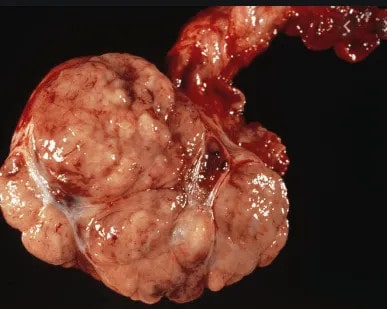

عکس سرطان بیضه